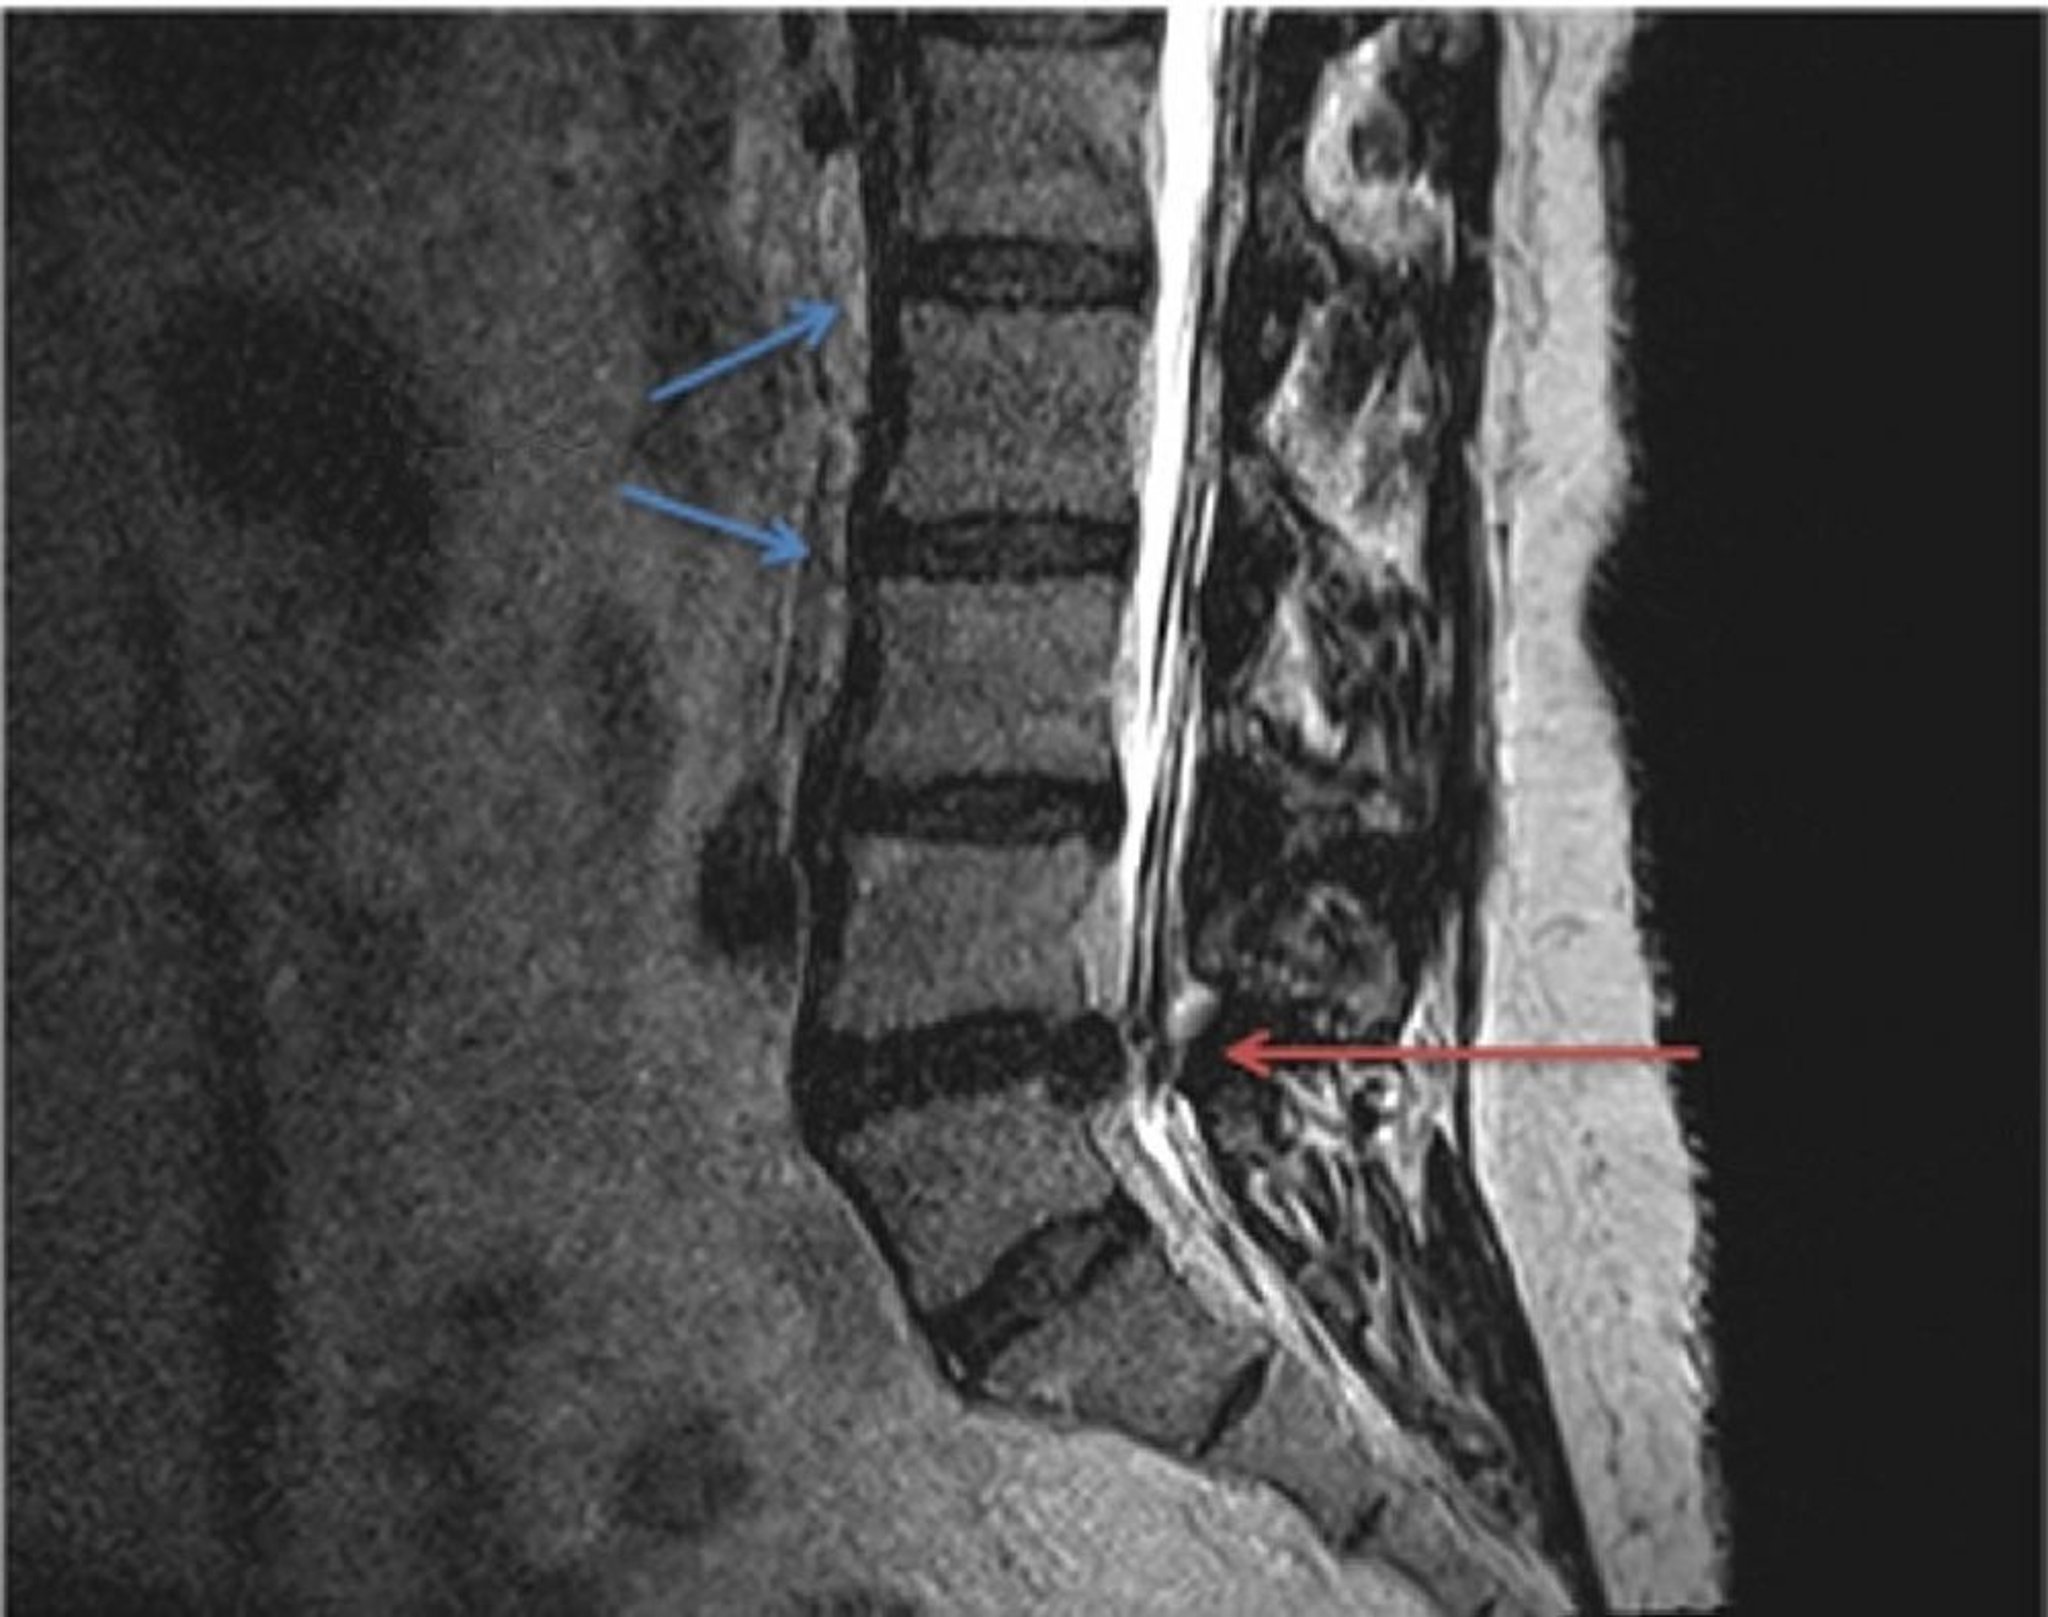

Hernie discale (IRM)

Comparaison de la normale (flèches bleues) et de la hernie discale lombaire dans une IRM pondérée en T2. La hernie discale, située entre les vertèbres L4 et L5 (flèche rouge), est en train de pincer le nerf spinal qui s'étend à partir de la moelle épinière, entraînant une pression et une douleur localisée ou irradiante.